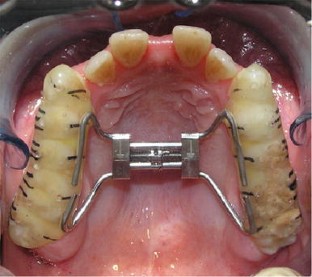

Fig. 3